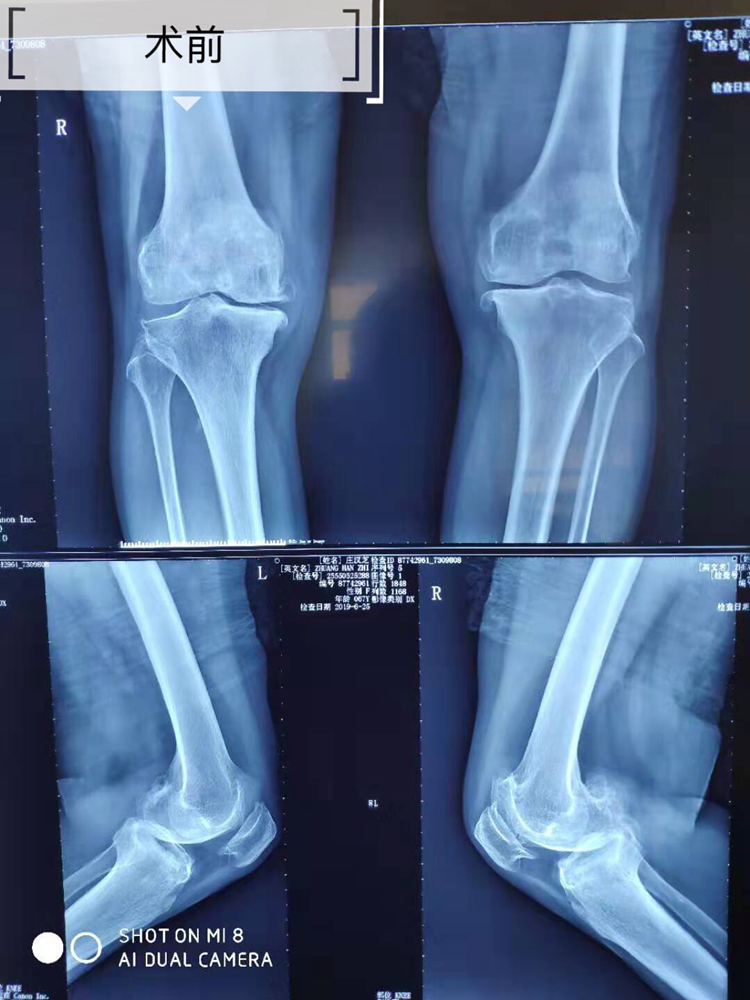

据悉,该患者因重度膝关节骨关节炎,行走时剧烈疼痛,患者因此饱受膝关节疼痛折磨多年,辗转多地诊治未见疗效。近年来,患者疼痛程度日益加重,严重影响生活质量,遂到我院骨伤科求诊。入院完善各项检查后,骨伤科手术团队经研究后制定了治疗方案——为患者行“双膝关节置换术”。经过医护人员两小时的共同努力,手术顺利完成。术后患者双膝关节疼痛得到了明显缓解,家属感激不已,连连称赞。

目前,我院已能常规开展“重度膝关节骨关节炎双膝关节置换术”。该技术的推广与实施,再次彰显了我院先进的诊疗水平及技术优势,使昭通市及周边地区的患者不出家门就可以享受到先进的医疗服务。(供稿/骨伤科 刘大泽)